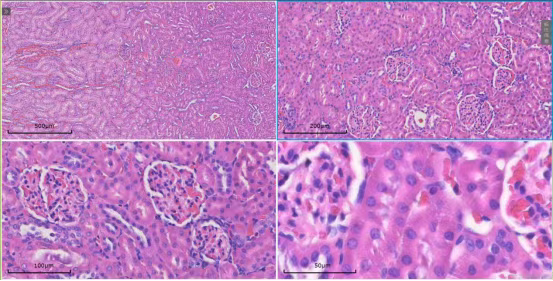

扫描系统覆盖4倍、10倍、20倍及40倍等多个物镜倍数。无论是在4倍镜下观察组织全貌,还是切换至40倍油镜分析细胞亚结构,系统均能确保图像清晰、细节无损,为形态学定量分析给予可靠依据。

针对超大尺寸切片,系统可自动进行图像采集与无缝拼接,生成完整的全景数字切片。研究者可在全景图中快速定位,并直接放大至目标区域进行高倍数观察,实现“整体布局-局部特征”的一体化分析。

以肾脏研究为例,该服务还可给予全景扫描与多切面对比的特色解决方案,以满足深度研究需求。

肾全景 横切-纵切